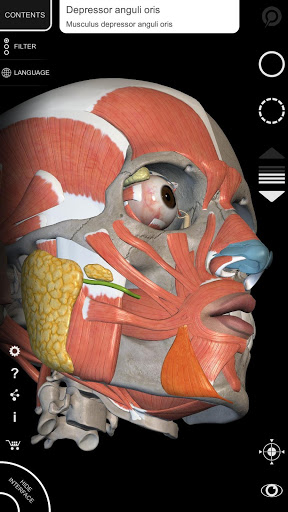

"Anatomy 3D Atlas" vous permet d'étudier l'anatomie humaine de manière simple et interactive.

Grâce à une interface simple et intuitive, il est possible d'observer chaque structure anatomique sous n'importe quel angle.

Les modèles anatomiques 3D sont particulièrement détaillés et avec des textures jusqu'à une résolution de 4k.

• Système musculo-squelettique

• Visualisation des muscles à travers des niveaux de couches depuis les plus superficielles jusqu'aux plus profondes

• En sélectionnant un modèle ou une épingle, le terme anatomique associé apparaît

• Description des muscles : origine, insertion, innervation et action